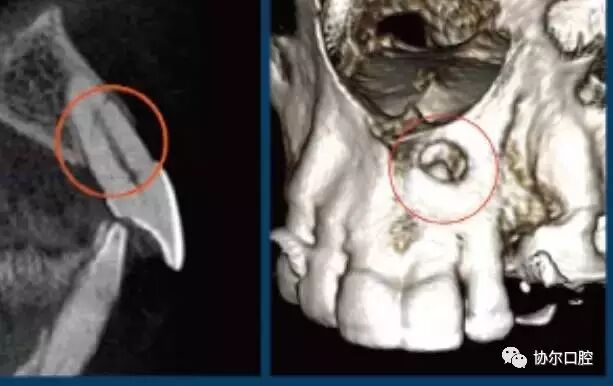

Quantum iQ的专利图像处理技术提供平滑的软组织影像,并最大程度的显示硬组织和骨结构的细节及对比。

完整的骨结构TMJ分析

真实可靠的牙周影像

高质量的牙体牙髓

一句话,使用KaVo 3D eXam i独有的软件可以准确而高效地实现对种植、基台、修复体的设计,帮助种植、修复、牙体牙髓以及正畸计划的制定和实施。完整的骨结构TMJ分析,精确的气道分析是很多三合一CBCT达不到的,也是医生在诊断中容易忽视的。工欲善其事,必先利其器,好的影像学检查资料,将为医生的治疗锦上添花。